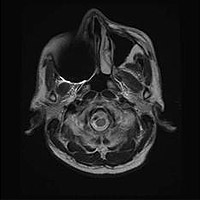

AIR Recon DL画像の一例

脳

頚動脈プラーク